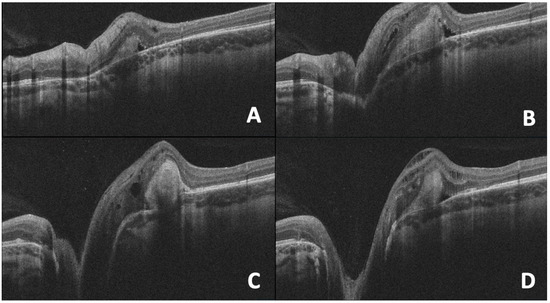

Applications of Optical Coherence Tomography in Optic Nerve Head Diseases: A Narrative Review

Optical coherence tomography (OCT) is a non-invasive imaging tool that is currently used in the evaluation and management of neuro-ophthalmic disorders. The detailed ability to visualize the optic nerve head, peripapillary retinal nerve fiber layer, and the macula, including the ganglion cell layer, [...] Read more.

Optical coherence tomography (OCT) is a non-invasive imaging tool that is currently used in the evaluation and management of neuro-ophthalmic disorders. The detailed ability to visualize the optic nerve head, peripapillary retinal nerve fiber layer, and the macula, including the ganglion cell layer, allows for both qualitative and quantitative analysis of optic nerve diseases. This review covers the technical aspects of OCT and related imaging techniques in neuro-ophthalmology and discusses its use in common optic nerve head diseases such as optic disc drusen, optic disc coloboma, and elevated intracranial pressure. It also explores emerging OCT angiography applications in these disorders. Full article

Show Figures

Figure 1